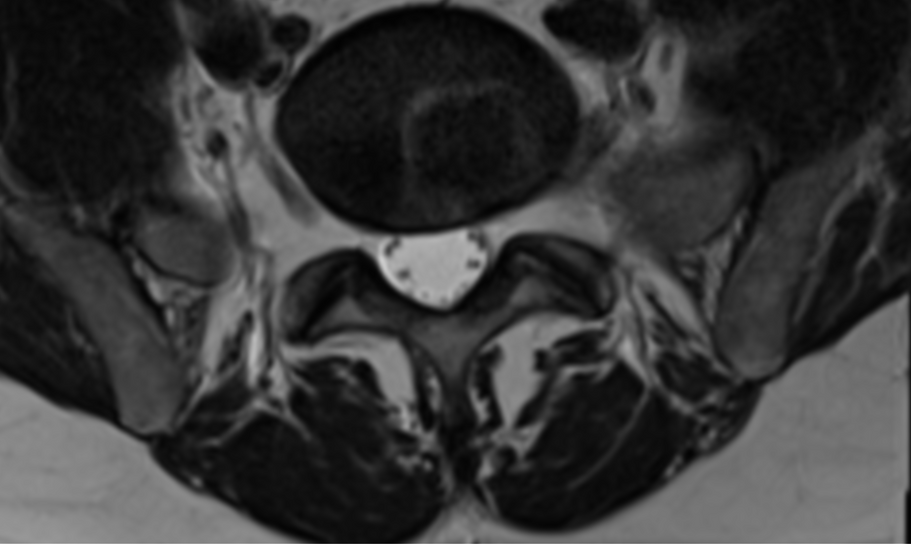

Cas clinique 4

Diagnostic

Bonjour, je suis.